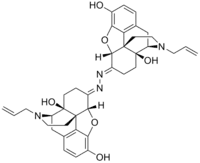

The pharmacodynamic response to an opioid depends upon the receptor to which it binds, its affinity for that receptor, and whether the opioid is an agonist or an antagonist. For example, the supraspinal analgesic properties of the opioid agonist morphine are mediated by activation of the μ1 receptor; respiratory depression and physical dependence by the μ2 receptor; and sedation and spinal analgesia by the κ receptor. Each group of opioid receptors elicits a distinct set of neurological responses, with the receptor subtypes (such as μ1 and μ2 for example) providing even more [measurably] specific responses. Unique to each opioid is its distinct binding affinity to the various classes of opioid receptors (e.g. the μ, κ, and δ opioid receptors are activated at different magnitudes according to the specific receptor binding affinities of the opioid). For example, the opiate alkaloid morphine exhibits high-affinity binding to the μ-opioid receptor, while ketazocine exhibits high affinity to ĸ receptors. It is this combinatorial mechanism that allows for such a wide class of opioids and molecular designs to exist, each with its own unique effect profile. Their individual molecular structure is also responsible for their different duration of action, whereby metabolic breakdown (such as N-dealkylation) is responsible for opioid metabolism.

Several semi-synthetic opioids were developed in Germany in the 1910s. The first, oxymorphone, was synthesized from thebaine, an opioid alkaloid in opium poppies, in 1914.[228] Next, Martin Freund and Edmund Speyer developed oxycodone, also from thebaine, at the University of Frankfurt in 1916.[229] In 1920, hydrocodone was prepared by Carl Mannich and Helene Löwenheim, deriving it from codeine. In 1924, hydromorphone was synthesized by adding hydrogen to morphine. Etorphine was synthesized in 1960, from the oripavine in opium poppy straw. Buprenorphine was discovered in 1972.[228]

Morphinan derivatives